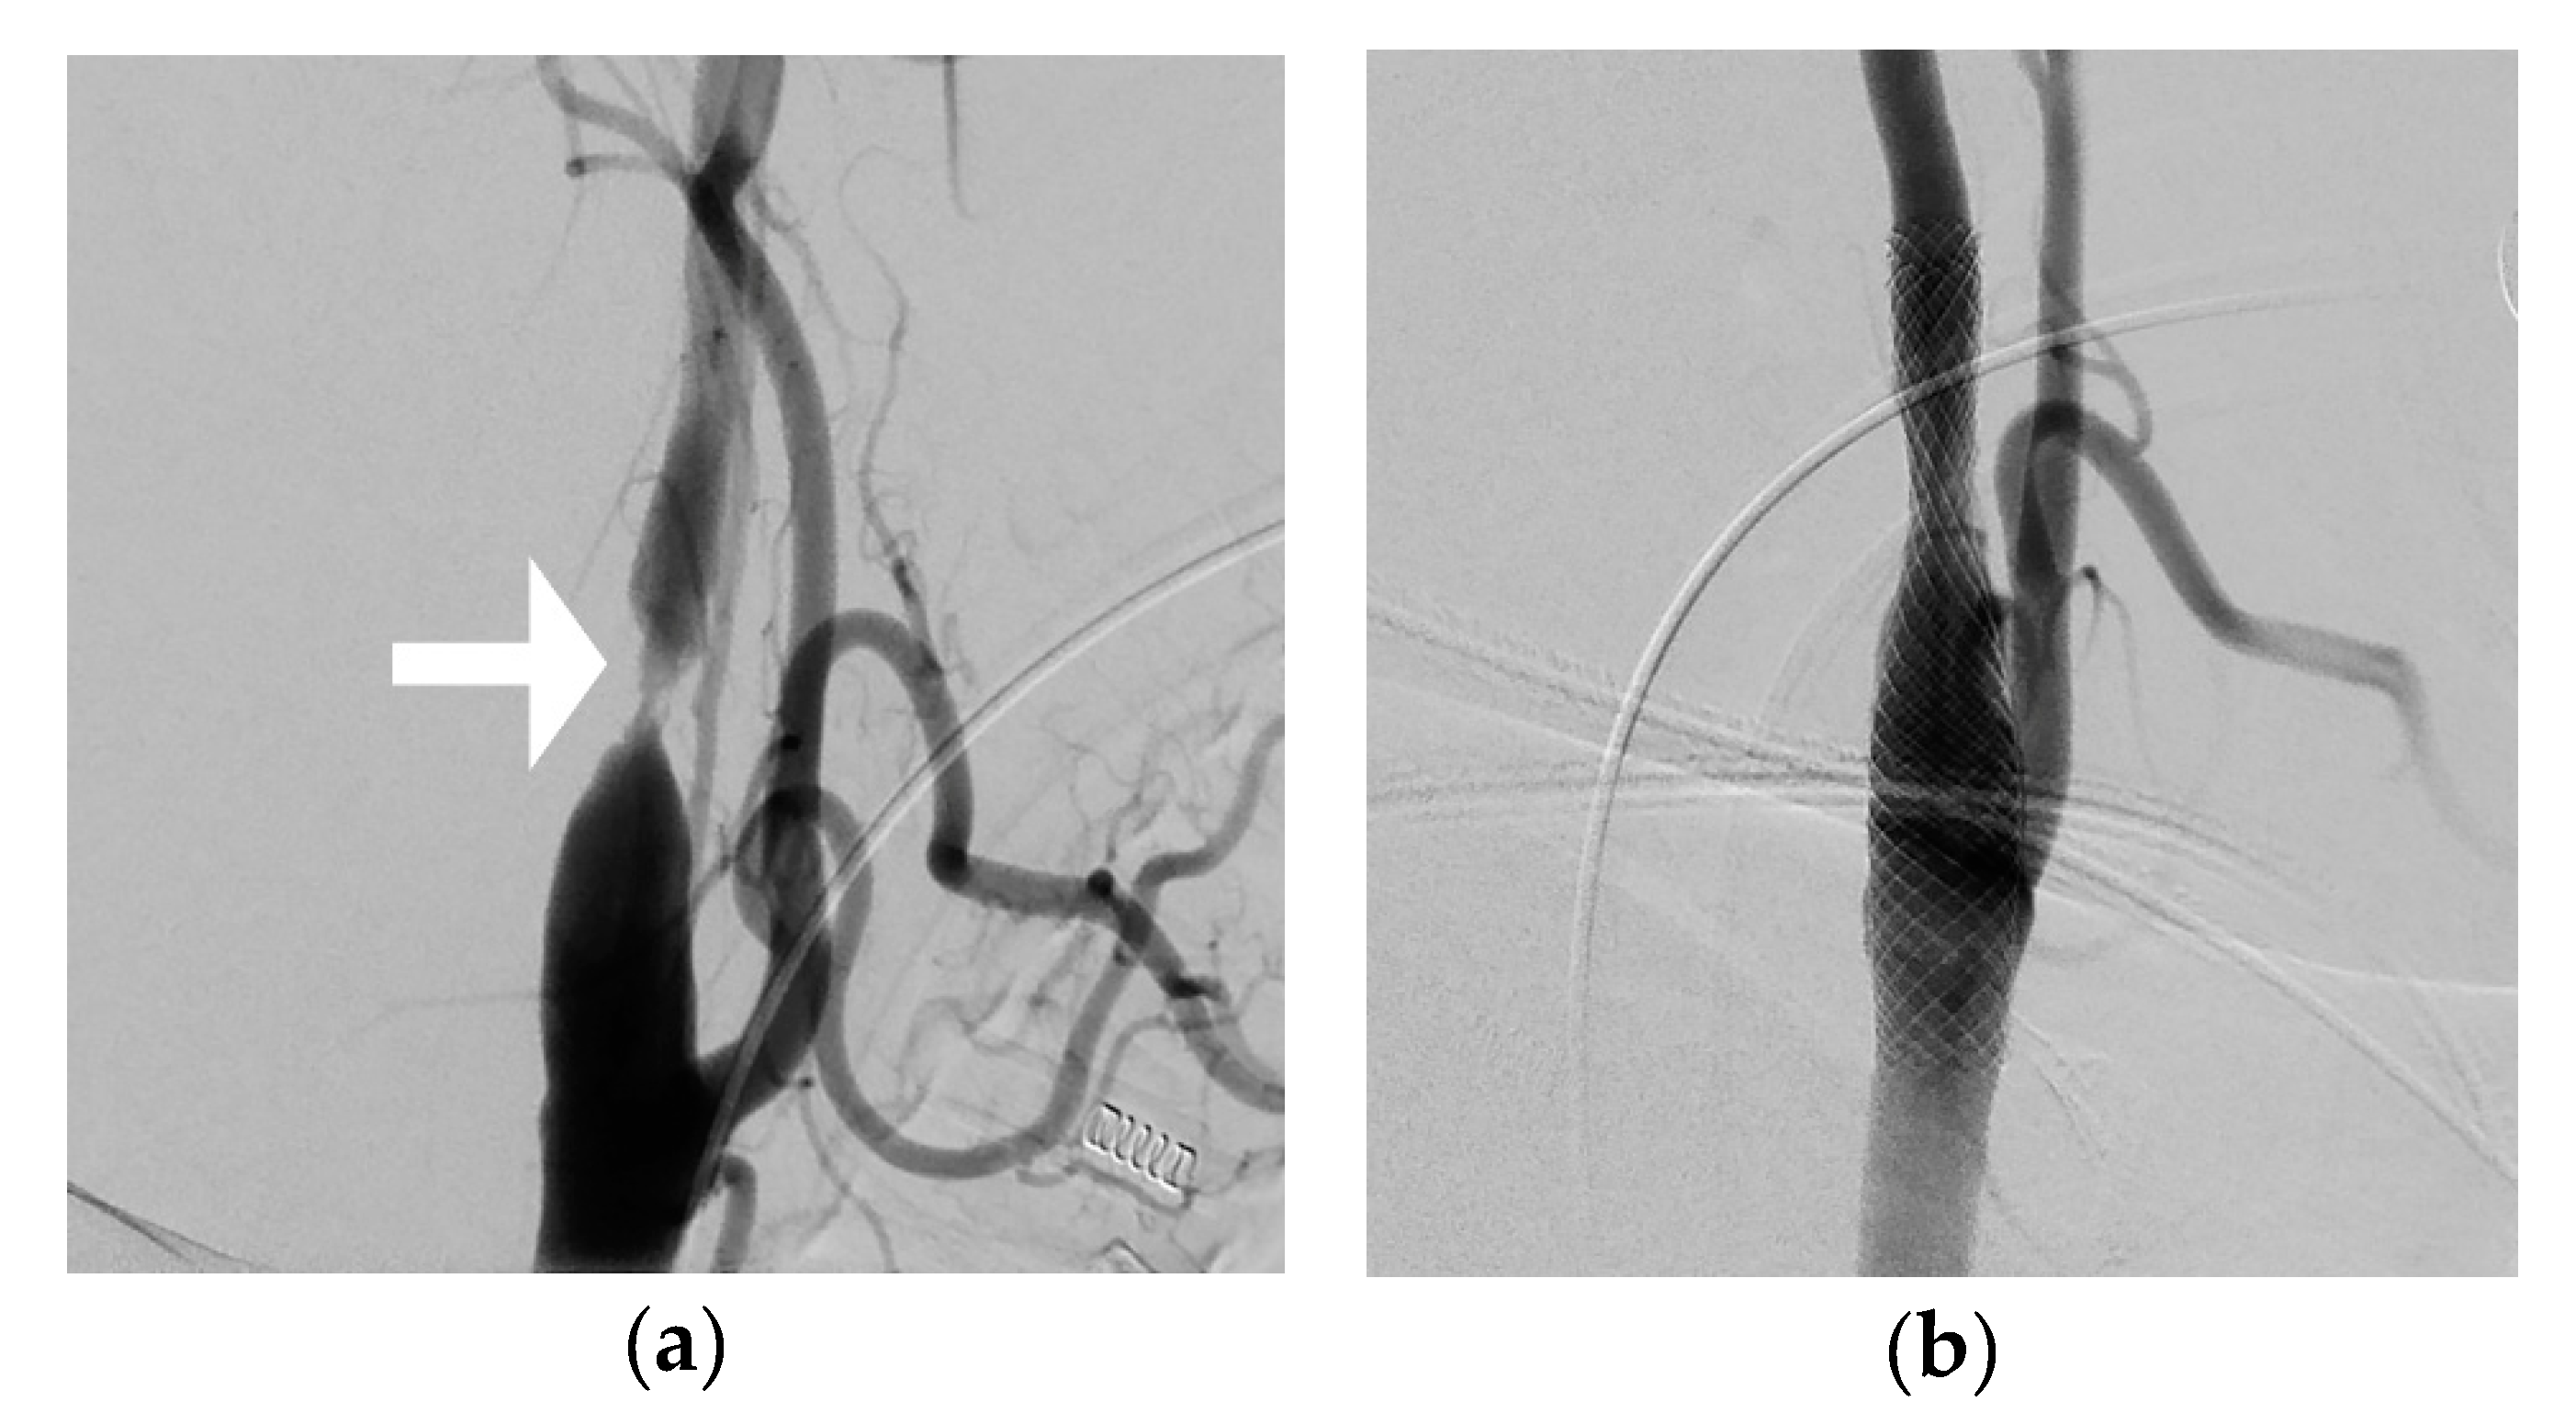

Carotid Stenosis Assessment with Vector Concentration before and after Stenting

| Mean stenosis degree (%) | 72.4 (8.2) | 13.3 (7.0) | −59% [−52%; −67%] | <0.001 |